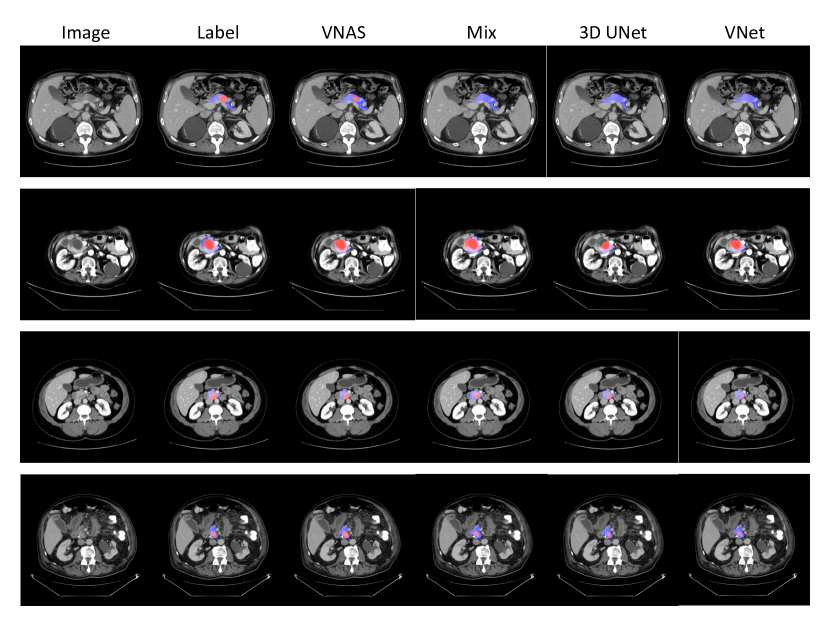

Refer to caption

Figure 4: The visualization illustration of predicted segmentation for “VNAS”, “Mix”, “3D UNet” and “VNet” on the MSD Pancreas Tumors dataset, which is the most challenging task among our 333 segmentation tasks. Each row denotes a slice visualization from one case, and the specific cases numbers are “309”, “021”, “069” and “329” from top to bottom rows. The masked blue and red regions denote for the normal pancreas regions and tumor regions, respectively. Best viewed in color.

We illustrate the visualization results of different methods as given in Fig. 4 on the same slice of a same case for comparison in each row. 444 cases ( #309#309\#309, #021#021\#021, #069#069\#069 and #329#329\#329) are chosen from the MSD Pancreas dataset, which are shown from top to bottom at each row, respectively. Note that the masked red and blue regions denote the pancreas tumor and normal pancreas regions, respectively. For the case #309#309\#309 in the first row, the proposed “V-NAS” successfully detects the tiny tumor regions while “Mix” and “3D UNet” totally fails and “VNet” almost fails by only finding several tumor pixels. For the case #021#021\#021, #069#069\#069 and #329#329\#329 from the 222nd to the 444th row, the searched architecture can semantically capture the tumor regions better because it can adaptively leverage both the rich 3D spatial context, the 2D within-slice information and the anisotropic structures.